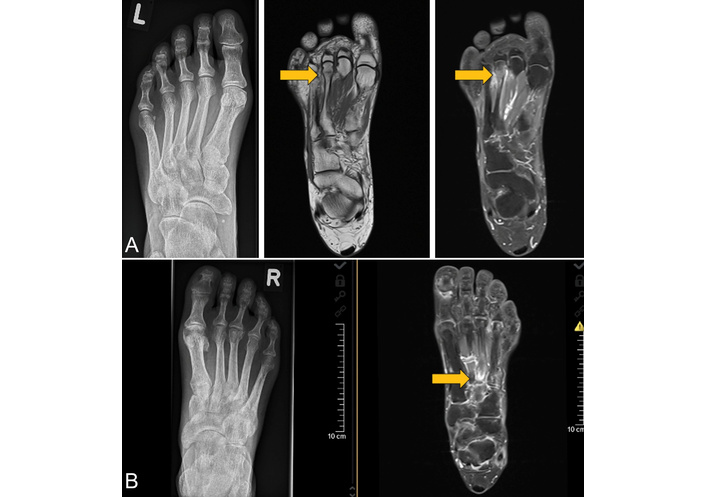

In a recent retrospective study published by our group [31], 1,752 MRI scans of consecutive patients presenting with foot pain were evaluated in two 2-year time periods. The patient group with IF was matched with controls with foot pain but no IF. Conventional radiographs and BMD as assessed by Dual Energy X-ray Absorptiometry (DXA) were available in the majority of patients. In total, 1,145 MRI of patients (median age 59 years, 83% women) with an inflammatory (65.4%) and 607 with a non-inflammatory (34.6%) RMD (median age 58 years, 80.8% female) were available. The most frequent diagnosis was RA (42.2%), while other patients had PsA (22.4%), axSpA (11.1%), or connective tissue disease (CTD; 7.6%) or other RMD such as gout. In 129 MRI scans of patients’ feet, IF was found (7.4%). Examples of IF are shown in Figures 1, 2, and 3. Importantly, there was no difference between time periods. Of interest, in patients with CTD (23%) and RA (11.4%), the prevalence of IF was highest. In comparison, more patients with an inflammatory than a noninflammatory RMD had an IF (9.1% vs. 4.1%, respectively; p < 0.001). Using conventional radiography, IF had only been detected in 25% of patients [30]. Patients with an IF had a low BMD and a history of fractures significantly more often than those without (42.6% vs. 16.2% and 34.9% vs. 8.6%, respectively).

A conventional radiograph (left figure) and MRI of two patients with an IF radiographically not detected. (A) Images of a 56-year-old woman with RA, disease duration 2.5 years. MRI of the left foot showing a subcapital fracture of the 3rd metatarsal head. The T1w MRI sequence (middle figure) shows the fracture as a hypointense line, while the contrast-enhanced fat-saturated T1w MRI sequence (right figure) reveals the reaction of the periosteum and an activation of the BM (gray arrows). This finding is similar in cases of periostitis and osteitis. (B) Images of a 61-year-old male patient with PsA, disease duration 6 years. The MRI shows a fracture of the base of the 3rd metatarsal in the right foot (gray arrow). The anatomy of this area makes the radiographic detection of fractures difficult. Therefore, MRI clearly is the method of choice to find fractures. The contrast-enhanced fat-saturated T1w MRI sequence reveals the fracture as a hypointense line, also with signs of reactive periosteal and BM activation. IF: insufficiency fracture; MRI: magnetic resonance imaging; BM: bone marrow; PsA: psoriatic arthritis; RA: rheumatoid arthritis; T1w: T1-weighted. Reprinted from [31]. © 2023 by the Journal of Rheumatology.